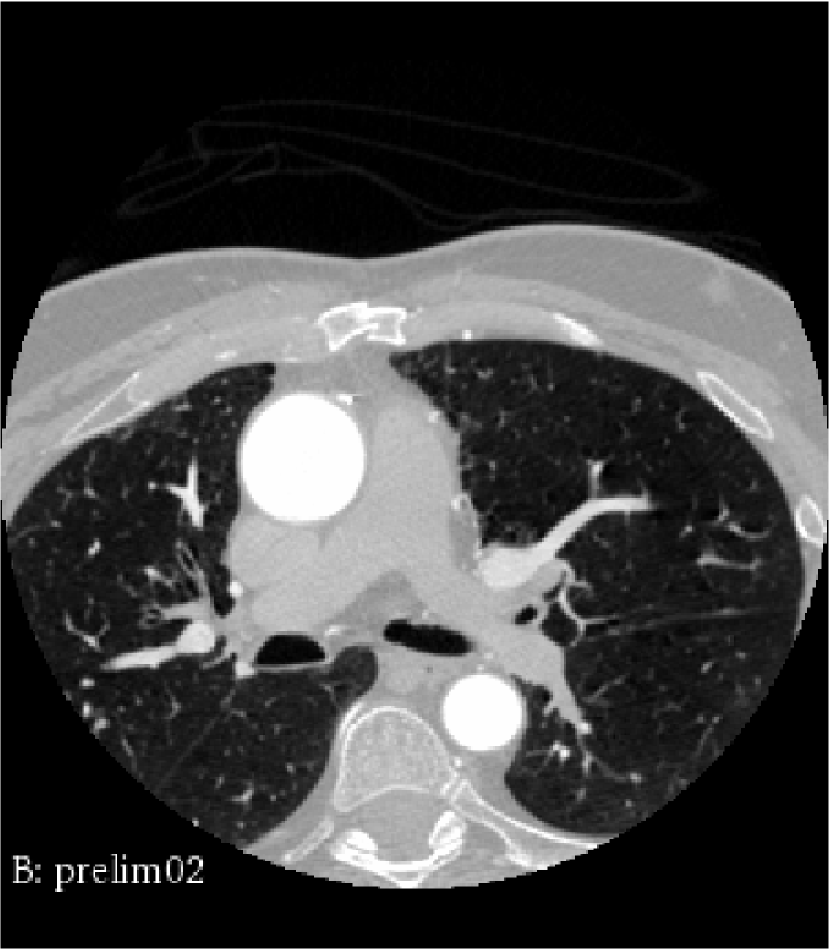

The data provided by the Sunnybrook Health Sciences Centre corresponding to this case, is a post-surgery computed tomography (CT) scan. The patient had at least three coronary arteries with occlusion ranging from mild to severe, thus, three different graft connections were made. These connections include right internal mammary artery (RIMA) grafted to bypass the blockage in left anterior descending artery (LAD) and two more connections made to first obtuse marginal artery (OM1) and posterior descending artery (PDA) separately using saphenuous veins (SV). Diseased coronary arteries and corresponding grafts, marked with different colors, are shown in figure 1.

We pre-processed the obtained medical image in order to alleviate image segmentation and geometrical reconstruction process. The pre-processing step is done in three stages, that are resampling, smoothing and enhancement, we refer the reader to Antiga et al. (Antiga et al., 2009) for details. The resampling stage aims at matching the resolution of the acquired image with the desired image segmentation process. Then, an anisotropic diffusion filter is used to reduce the high-frequency noise in the image and finally vessel enhancement filters are applied to enhance the visibility of vessel-shaped structures in comparison to other anatomical structures. Afterwards, using VMTK, we segment the pre-processed image into level sets, based on the colliding fronts approach. Then, a three-dimensional polygonal surface is generated through marching cube algorithm and is constructed by manually placing seed points according to visible intensity of the vessels. Due to the noise in clinical image and according to the visible intensity of coronary artery bypass grafts, the reconstruction process can add artificial artifacts corresponding to other parts of the cardiovascular system to the constructed geometries. We use VMTK smoothing filters to remove deformities to much extent, however the resulting tubular structures do not have sufficiently regular boundary, as is visible in the third figure, titled surface smoothed out using VMTK, in figure 2.